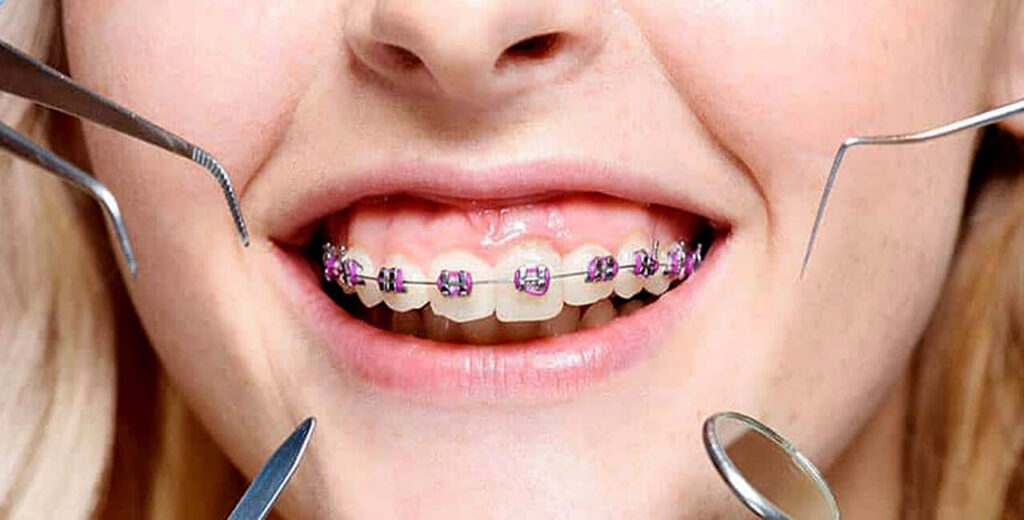

Overview of Orthodontics

We are a professional and affordable dental practice in Hyderabad offering an extensive range of dental services at the Hospital, including cosmetic, orthodontic, periodontic, endodontic, implant and cosmetic teeth whitening treatments, other specialist dental services.